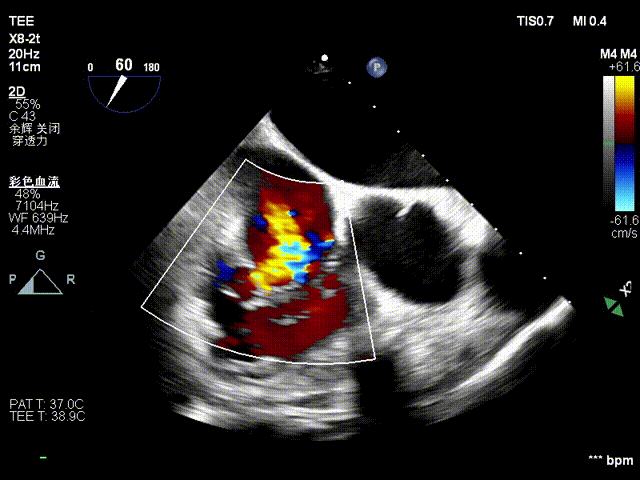

术前超声

术后超声